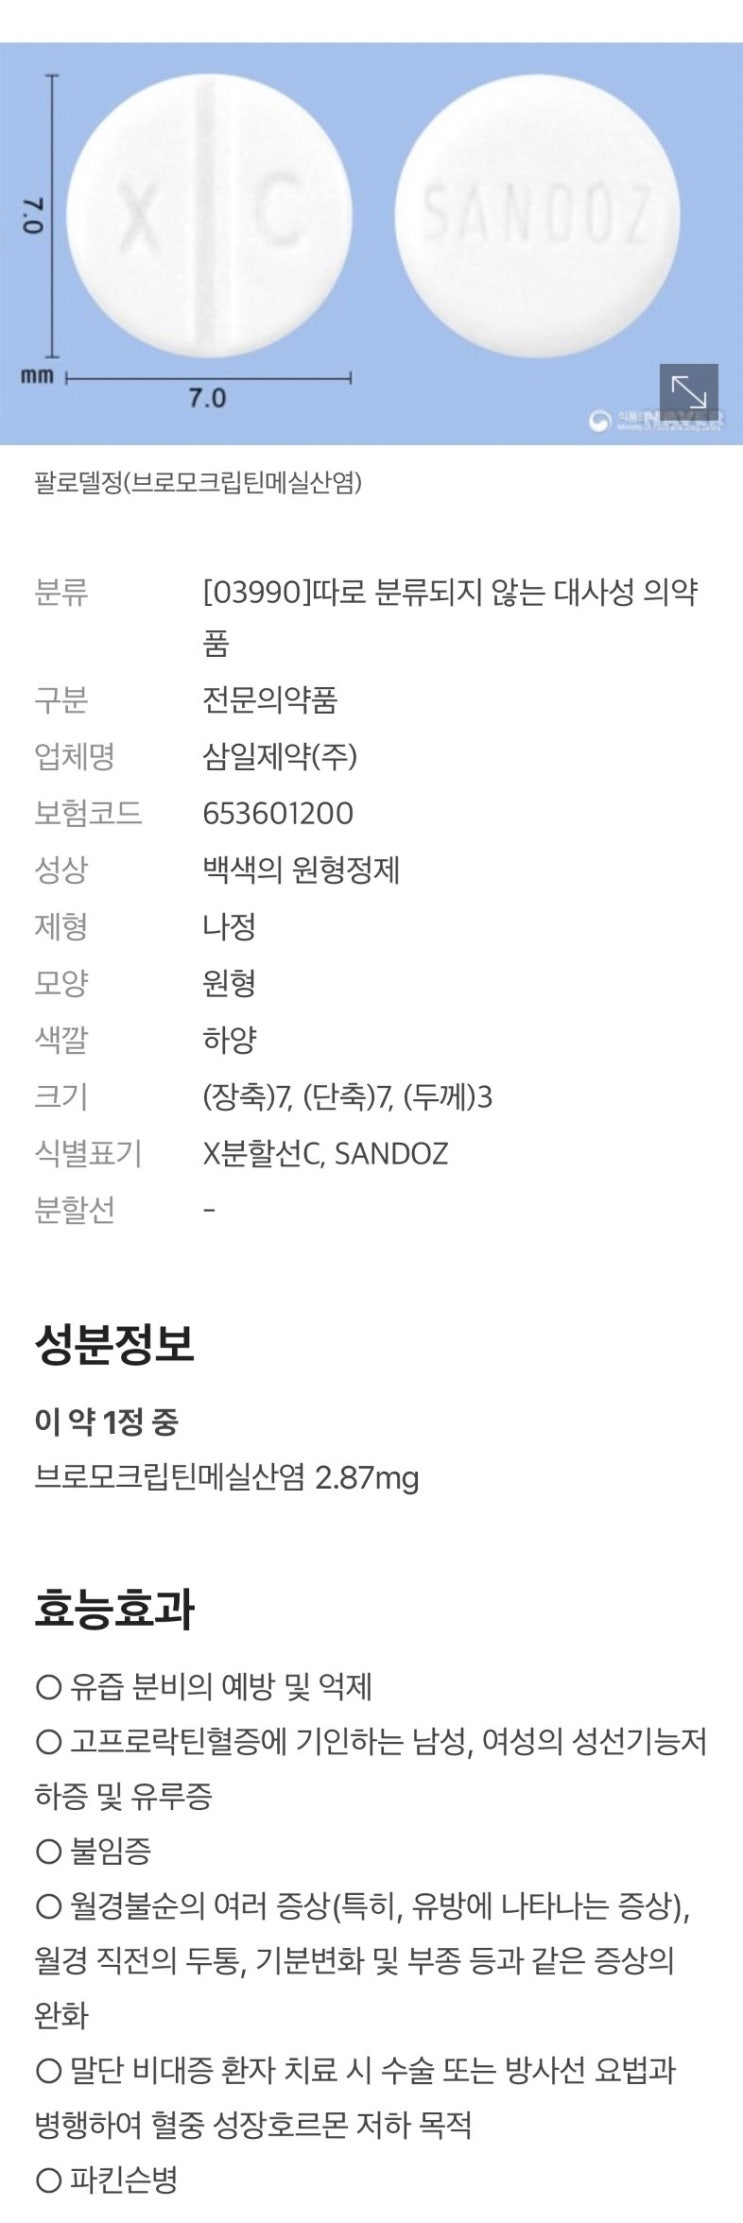

난포를 키우기 위해 페마라를 5일간 복용하고 배란초음파를 확인하러 병원을 방문했다. 다행히 난포도 잘 ...